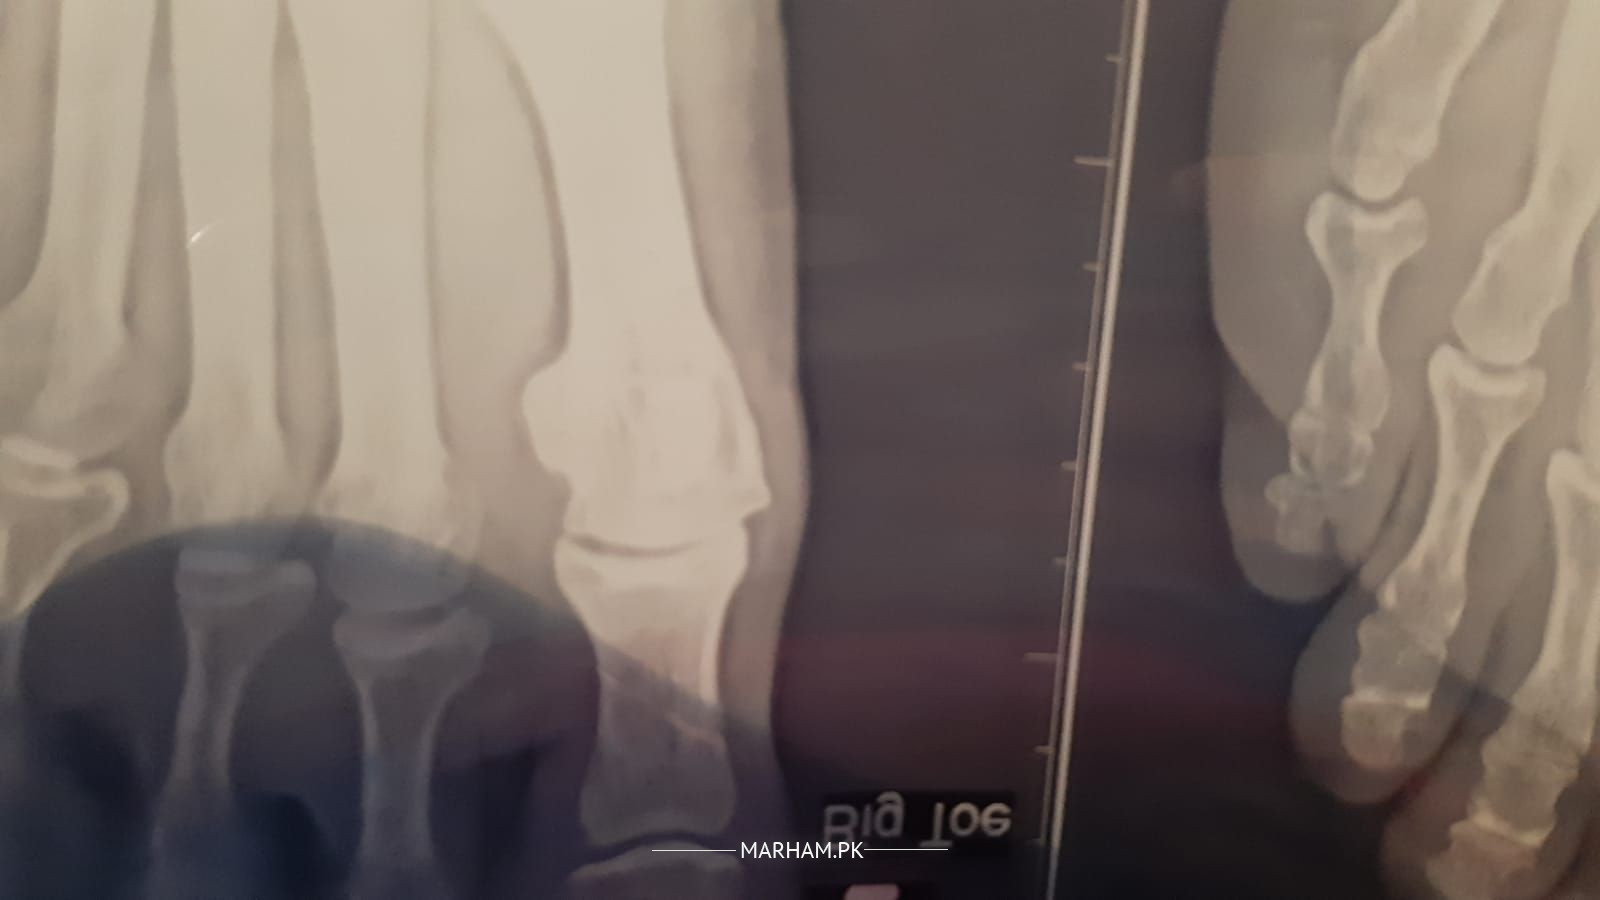

meri ami k paon k anghothay ki haddi barh gyi hai 6 months se treatment chal rha hai laikin woh worst se worst horhi hai I am attaching x-rays please check and consult me k kia krna chahiye. unko bht dard hai.

Assalam o Alaikum. After workup, surgery seems to be the only option ma'am. Barrhi hui haddi trim karnay kay liyay.

She has arthritis and I can sort it out with simple non surgical means make an appointment to see me on 042-32591427,